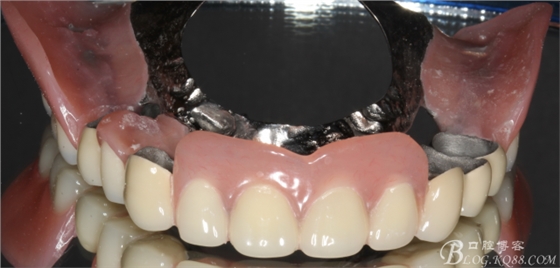

經(jīng)過(guò)系統(tǒng)的治療,患者的牙周狀況得到明顯的改善,改變冠根比例之后的基牙沒(méi)有明顯的松動(dòng),

考慮治療方案:

上頜基牙比較分散,選擇 5顆基牙的套筒冠修復(fù),

鈷鉻合金金屬內(nèi)冠

套筒冠外冠

下頜由于44治療之后,松動(dòng)度改善不大,原來(lái)的咬合創(chuàng)傷比較大,不能承擔(dān)較大的(牙合)力,選擇覆蓋義齒,把它磨短平齊牙齦,

其他牙比較集中,選擇雙端球帽式附著體修復(fù)雙端游離缺失

修復(fù)后效果圖,

說(shuō)到咬合重建確是一個(gè)很復(fù)雜的命題,他需要醫(yī)生有很厚的修復(fù)功底,對(duì)待患者的咬合有一個(gè)正確的評(píng)價(jià),根據(jù)經(jīng)驗(yàn)對(duì)垂直患者的咬合距離得以正確的回復(fù)和重建。這個(gè)病例就是對(duì)原來(lái)的垂直距離抬高了2mm,修復(fù)后患者感覺(jué)非常舒服。